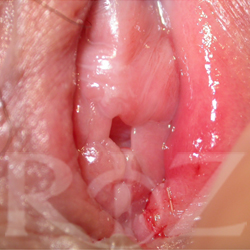

• 치료 전 사진

치료 후 사진

나이 : 22 / 출산경력 : 0 / 이름 :박OO

레이저처녀막수술  LMH™(Laser Micro Hymenoplasty™)

- Before :  처녀막 부분이 손상되어 질 입구가 벌어진 상태

- After :  LMH 수술 후 처녀막이 거의 흔적없이 완벽하게  복구 됨